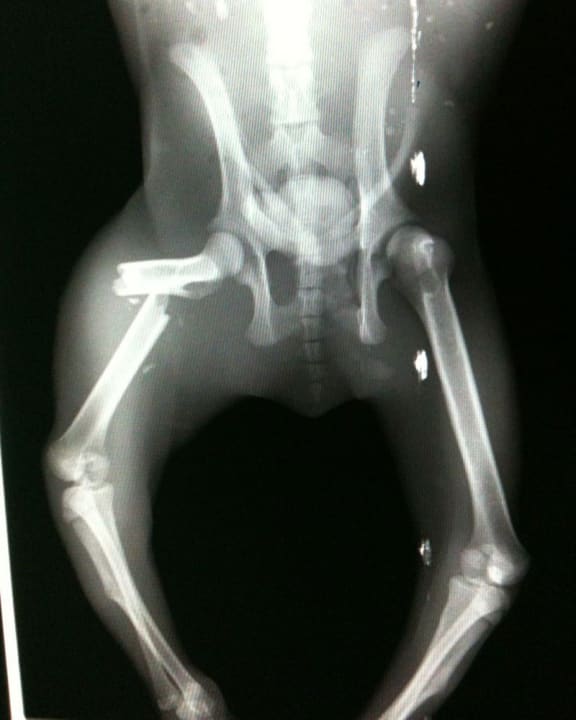

X-ray of koala with leg fracture from vehicle strike, southeast Queensland, April 2017. The koala was from the Moreton Bay region and had orthopaedic repairs on their broken limbs and was luckily able to be released

© Endeavour Veterinary Ecology